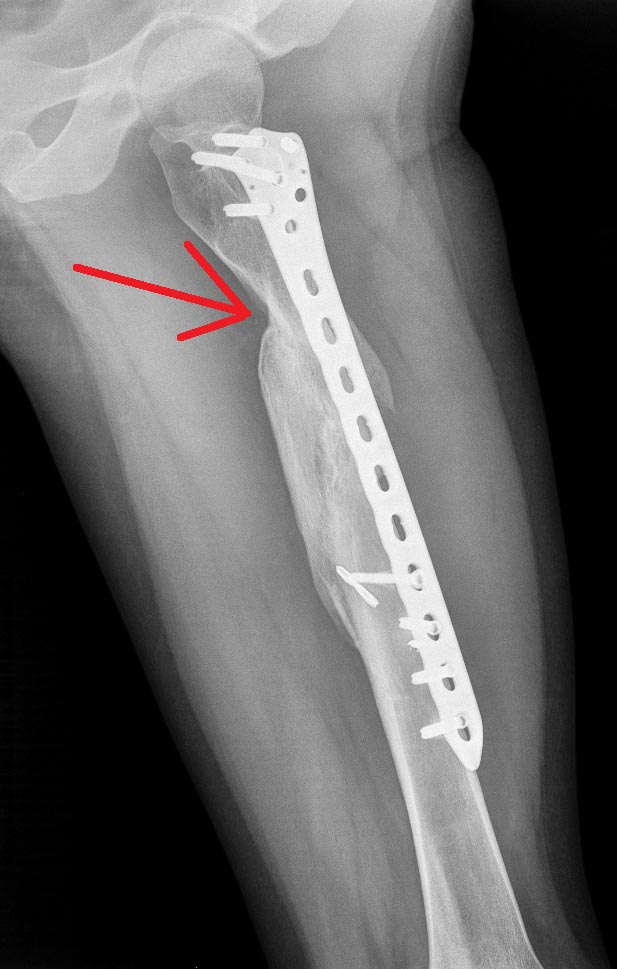

Доброго времени суток, уважаемые коллеги!Просим помощи. Пациентка 24 г. Травма 2 года назад, операция- малоинвазивный остеосинтез бедренной мыщелковой пластиной. В настоящий момент пациентка намерена удалить пластину (мешает). Смущает участок, отмеченный стрелкой- выдержит ли полную нагрузку. Стоит ли удалять пластину? Спасибо!

Главным критерием для удаления пластины является вес и процесс вовлечения диафиза бедра! На рентгенограмме контур мягких тканей не говорит об избыточном весе, и вовлечение поперечнике диафиза на самом тонком месте, где указано стрелкой, не превышает 40%. Это цифра принята для расчета нужды в дополнительной фиксации при вовлечении диафиза в патологический процесс. Если имеется дефект диафиза больше, чем 40% диаметра кортекса, тогда рекомендуется профилактическая фиксация, гвоздем или пластиной!

Всем привет! Что и как в голове у пациентке вам видней по поводу ее желания удалить пластину, а по R-граммам пластину удалить можно вокруг винтов проксимального отломка имеется резобция а значит она уже ходит на сросшемся переломе!